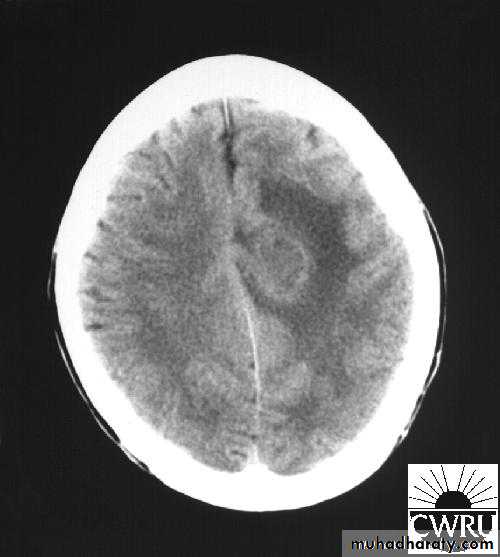

Brain Abscess CT without contrast

Brain Abscess CT with contrast

• B. Radiological Investigations:• CT or MRI is the investigation of choice.

• CT Brain is performed with and without contrast.

• They will show a single (or multiple) space occupying lesion that is well delineated with an enhancing wall, with variable surrounding oedema.

• B. Radiological Investigations:• The differential diagnosis of a single brain abscess in CT or MRI is a solitary metastasis or cerebral infarction.